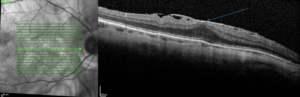

Diagnostic

Le diagnostic se fait à l’OCT (Optical Coherence Tomography).

Le diagnostic

Son diagnostic est fait à l’OCT (Optical Coherence Tomography).